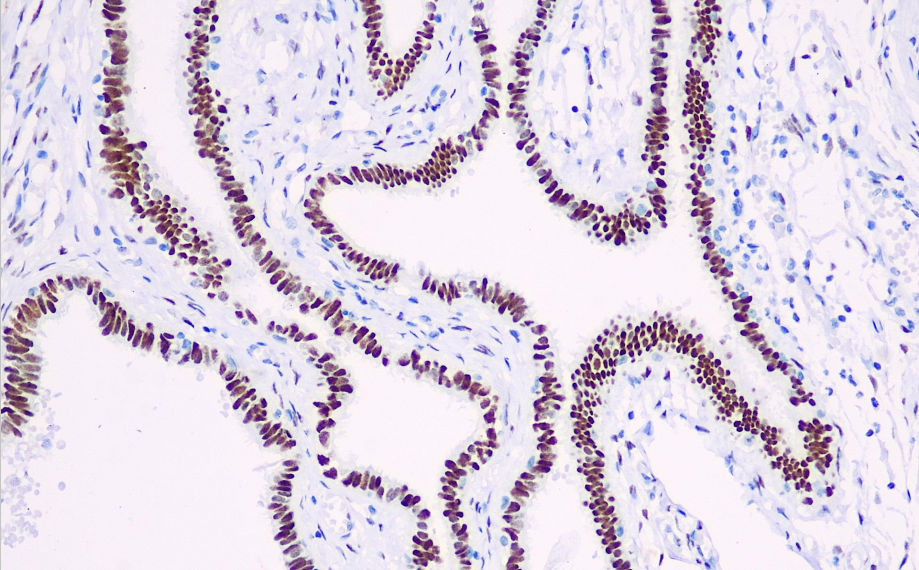

Cellular localization: nucleus

Positive control: Fallopian tube

WT1 is a tumor suppressor gene located on chromosome 11p13 that can identify mesothelial cell proliferation, malignant mesothelioma, ovarian cystadenocarcinoma, gonadal teratoma, nephroblastoma, and connective tissue proliferative small round cell tumors. It can be used to study small round cell tumors and Ewing's sarcoma that promote connective tissue proliferation, as well as primitive neuroectodermal tumors.

WT1 antibody reagents can specifically bind to WT1 molecular antigens. Immunohistochemistry kits containing WT1 antibody reagents are suitable for the precise diagnosis of mesothelial cell hyperplasia, malignant mesothelioma, ovarian cystadenocarcinoma, gonadal germ cell tumors, Wilms' tumor, and connective tissue proliferative small round cell tumors.